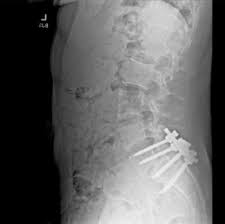

Even when Luigi Mangione was surrounded with people who cared about him, he was isolated by a spinal defect that dealt the athletic young man crippling pain and contributed to a jaundiced view of the American health-care system.

Mangione’s back X-ray

Ryan said that Mangione’s back pain was well known within the Surfbreak community. “It was a real problem for him, and he had to think about that in a way that most 24-year-old young men living in Hawaii would not have to worry about their health,” he said.

Mangione’s struggles with his back pain offer a glimpse into the interior life of a young man who outwardly lived a charmed existence — the scion of a wealthy family in Maryland who was valedictorian of his prestigious private school in Baltimore and earned degrees in computer science from the University of Pennsylvania….

In archived Reddit comments, Mangione doesn’t express anger toward UnitedHealthcare or other health insurers. But the posts chronicle his struggle over years to deal with back pain that became increasingly debilitating.

“From childhood until age 23, my back would always ache if I stood too long, but it wasn’t too bad,” he wrote in February. But as he entered his mid-20s, the pain began to disrupt his life, and he also struggled with cognitive issues.